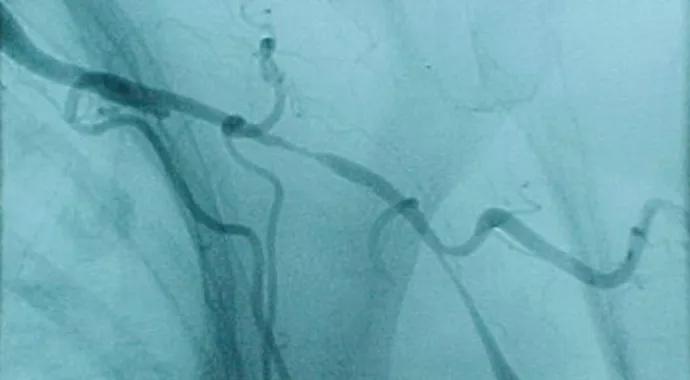

Figure 1. Angiogram in a woman complaining of arm claudication. Identical findings were present bilaterally. If you were told she was 28 years old, the diagnosis would be Takayasu’s arteritis. However, she was 82 years old and had giant cell arteritis.